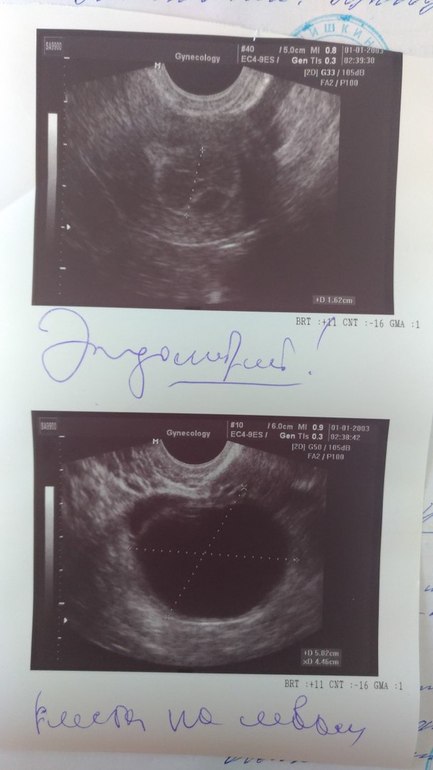

Девочки, сегодня была на узи после стимуляции.

Вот сегодня я была....

рассказываю.... ЖТ у меня ни какого не увидели...

Эндометрий у меня 1,5см просто ужас - слова узистки!

пр.яичник 3,0х2,7 d=2,6 d=2,4

левый 6,2х5,0 d=5,0х4,4, d=2,6, d=2,8

Кисты!!!!!!!!!! у меня они ни раз не наблюдались! и тем более они сейчас на обоих яичниках!

фото Узи